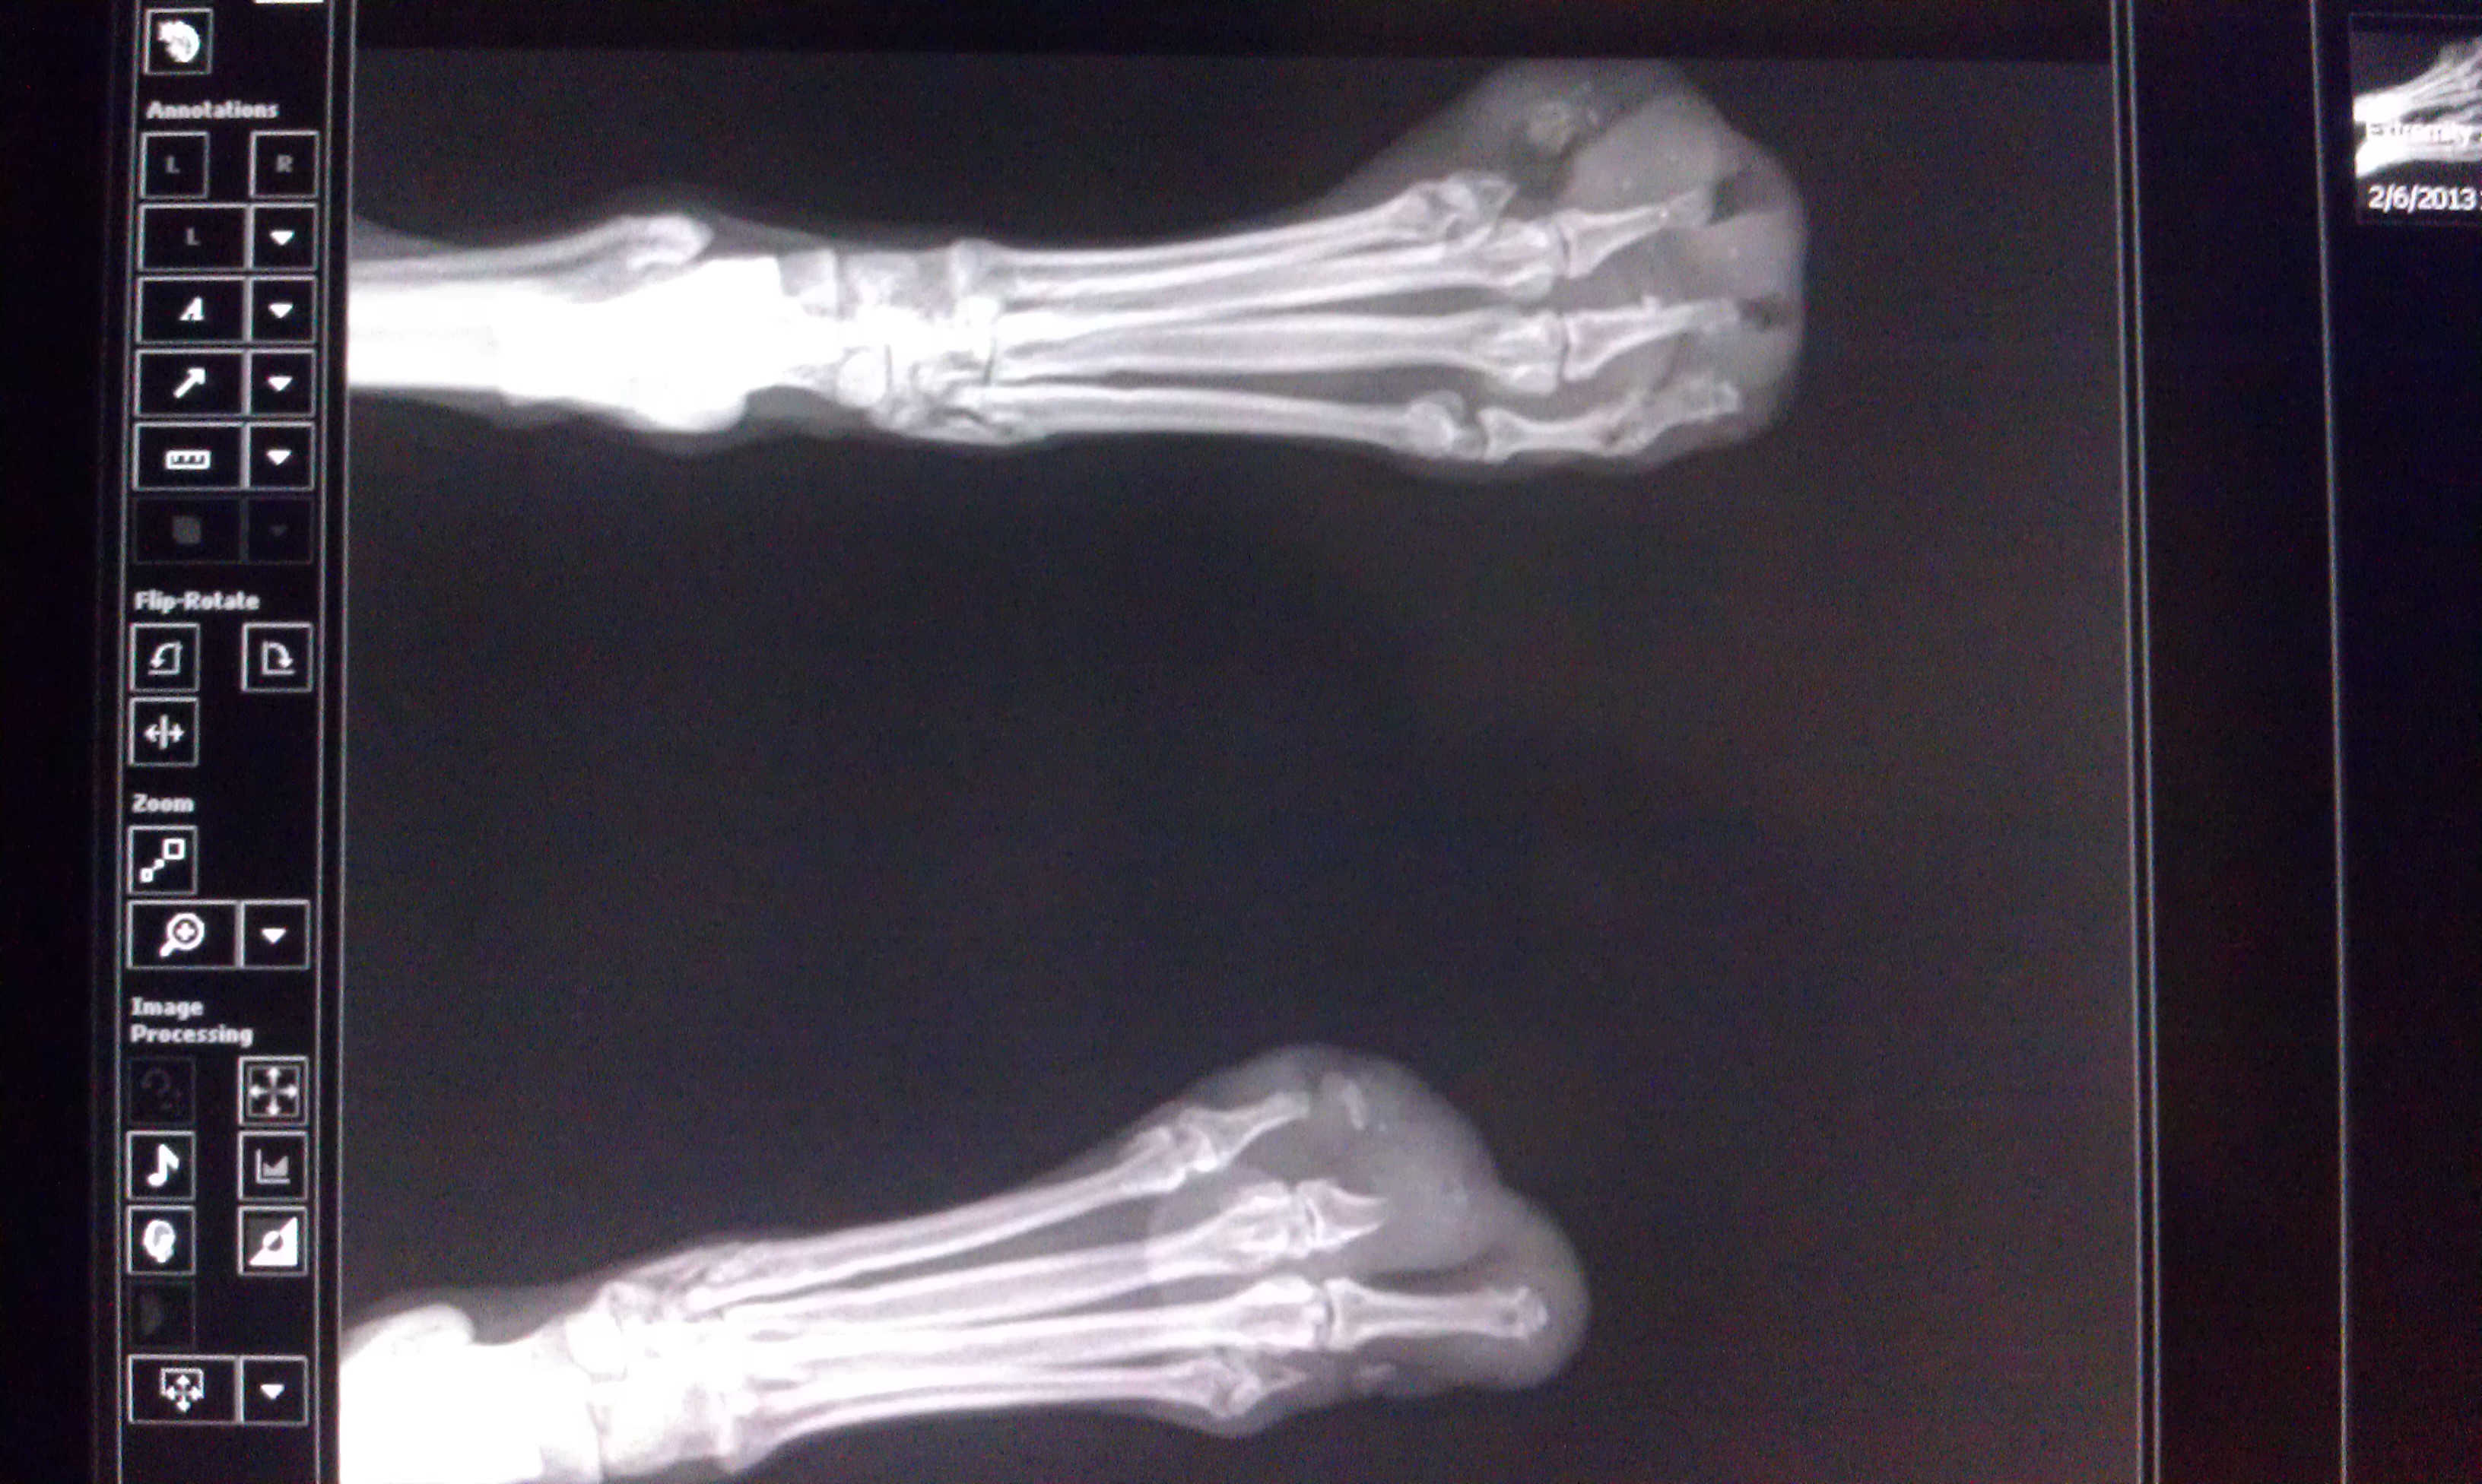

Shalimar started coming to us last winter. She’s a pom-mix, less yappy lap dog, more fox. She’s also a rescue from Arizona that around the office, became known as the foot dog. No one knows exactly what happened to her. The shelter that took her in found her wandering the desert streets, her paw pads scalded by the heat. But the radiographs we took show significant bone loss, and some have theorized that someone tried to declaw her by ripping out her nails. Either way her paws were severely infected with oozing drainage tracts on the tops and the bottoms of her feet.